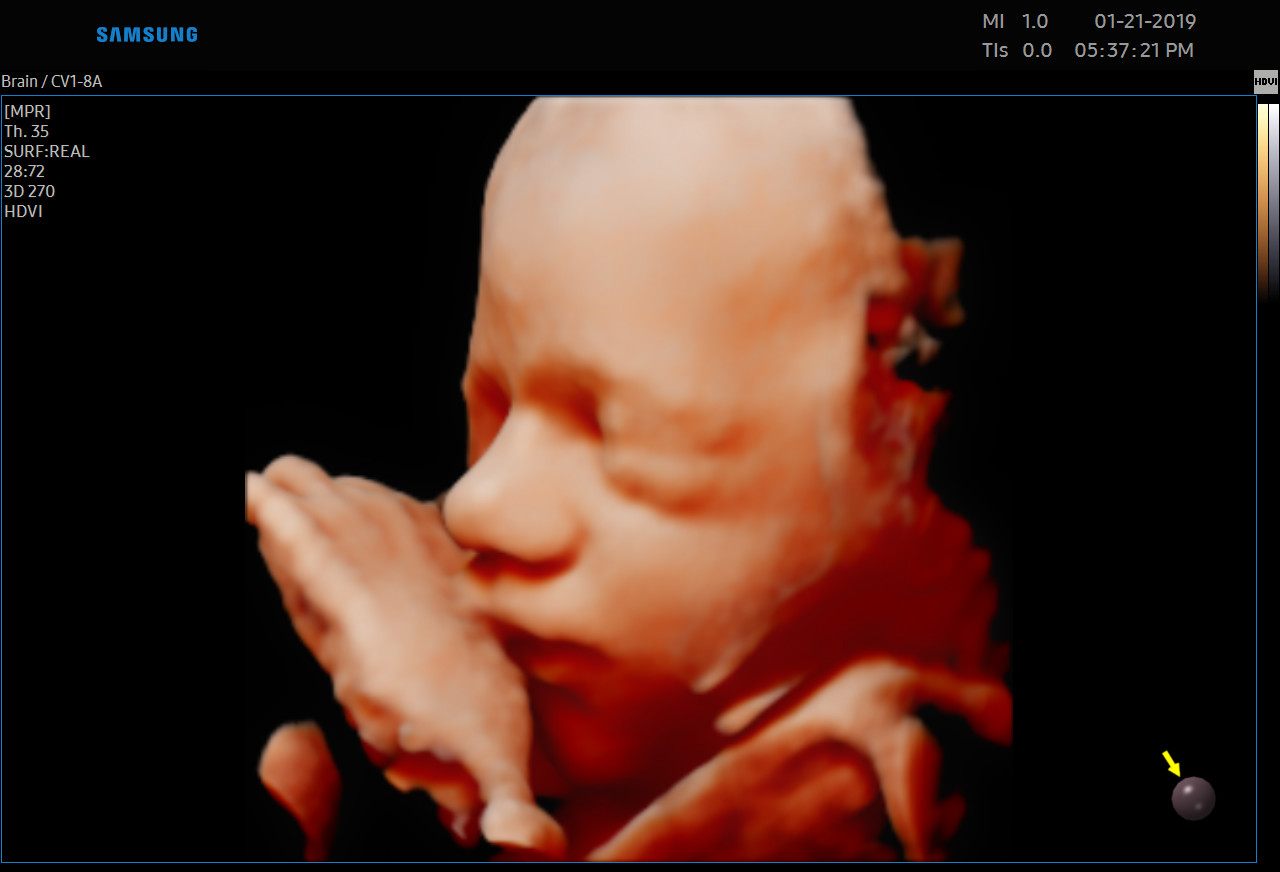

Każdą kobietę w ciąży otaczamy kompleksową opieką, czuwając nad jej zdrowiem oraz prawidłowym rozwojem płodu. Podczas regularnych wizyt, zlecamy odpowiednie badania laboratoryjne. Korzystając z najnowszej generacji aparatu USG, przeprowadzamy bardzo dokładną diagnostykę obrazową – łącznie z USG 3D/4D płodu.